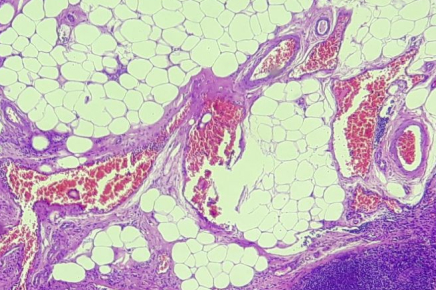

Laboratório Santa Clara é referência em Patologia, Citologia e Biologia Molecular. Aqui você encontra qualidade certificada, tecnologia e respeito por nossos parceiros e pacientes.

BIOLOGIA MOLECULAR

Diagnósticos avançados através da análise de DNA para detecção precoce de infecções, HPV, ISTs e alterações genéticas. Aqui tem!